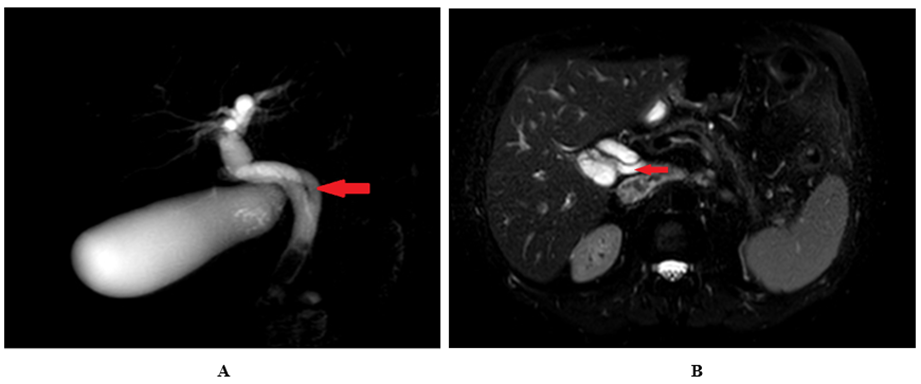

Ultrasound of the abdomen and pelvis revealed a dilated gallbladder with a thicker wall and with stones. The common bile duct (CBD) measured 15 mm in diameter, and stones were visible within it. Furthermore, the ultrasonography revealed the dilatation of the intrahepatic bile ducts. MRCP was conducted using 1.5 T MRI (Ingenia; Philips Healthcare, Best, the Netherlands) in the coronal, axial, and sagittal planes in accordance with standard protocol. T2-weighted sequences in multi planar reconstruction were used for the evaluation. Respiratory-triggered T2 SPAIR axial and T2 coronal sequences with slice thickness of 5 mm, comprising the liver and region, were acquired. The MRCP revealed a gallbladder with 3 small stones and a 16 mm-diameter common bile duct (CBD) with four stones visible inside. Furthermore, coronal oblique 3D MRCP showed posterior spiral course of cystic duct with medial insertion with CHD (Figure 1)

Figure 1: Coronal oblique 3D MR cholangiopancreatography (A and B) and T2w-SPAIR sequence in axial plane (C) show posterior spiral course of cystic duct (red arrow) with medial insertion with CHD.